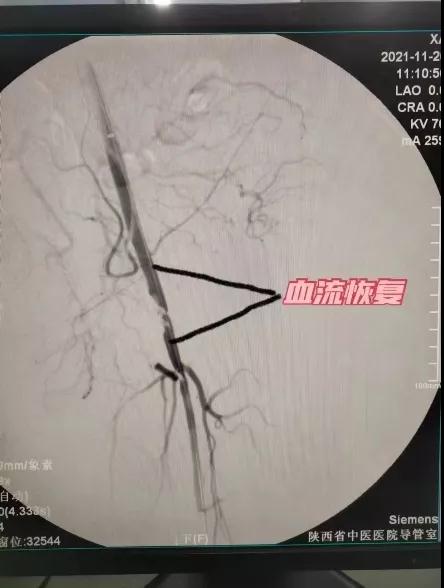

此图可看出患者左侧肢体动脉闭塞,造成肢体缺血血氧,而发生下肢疼痛、困重,局部皮肤冰凉、青紫等症状,随即采用动静脉血栓清除系统,对病灶血管血栓抽吸(如下图):

患者局部血管打通,血流可正常通过闭塞段,术后患者立即感左足疼痛减轻,下肢困重缓解,皮温恢复正常,皮肤颜色恢复正常,患者可下床正常行走,急性闭塞血管被重新打通。